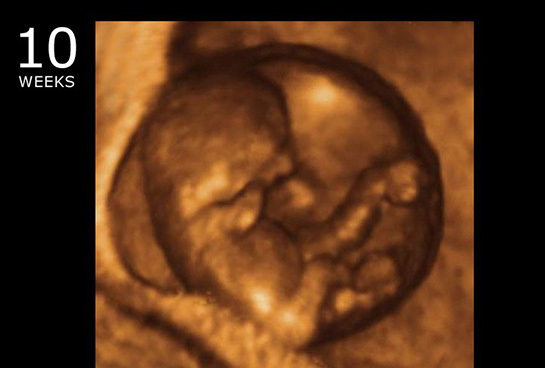

Tanı Yöntemleri Mol gebelik tanısı, genellikle ultrason ve kan testleri ile konur. Ultrason, plasentanın anormal büyümesini ve embriyonun gelişim durumunu değerlendirmek için kullanılır. Ayrıca, beta-hCG (human chorionic gonadotropin) hormonu seviyelerinin izlenmesi de tanı sürecinde önemlidir. Bu hormonun seviyeleri, mol gebelik durumunda genellikle normalden daha yüksektir. Tedavi Seçenekleri Mol gebelik tedavisi, durumun türüne ve hastanın genel sağlığına bağlı olarak değişkenlik gösterebilir. Genel tedavi yöntemleri şunlardır: